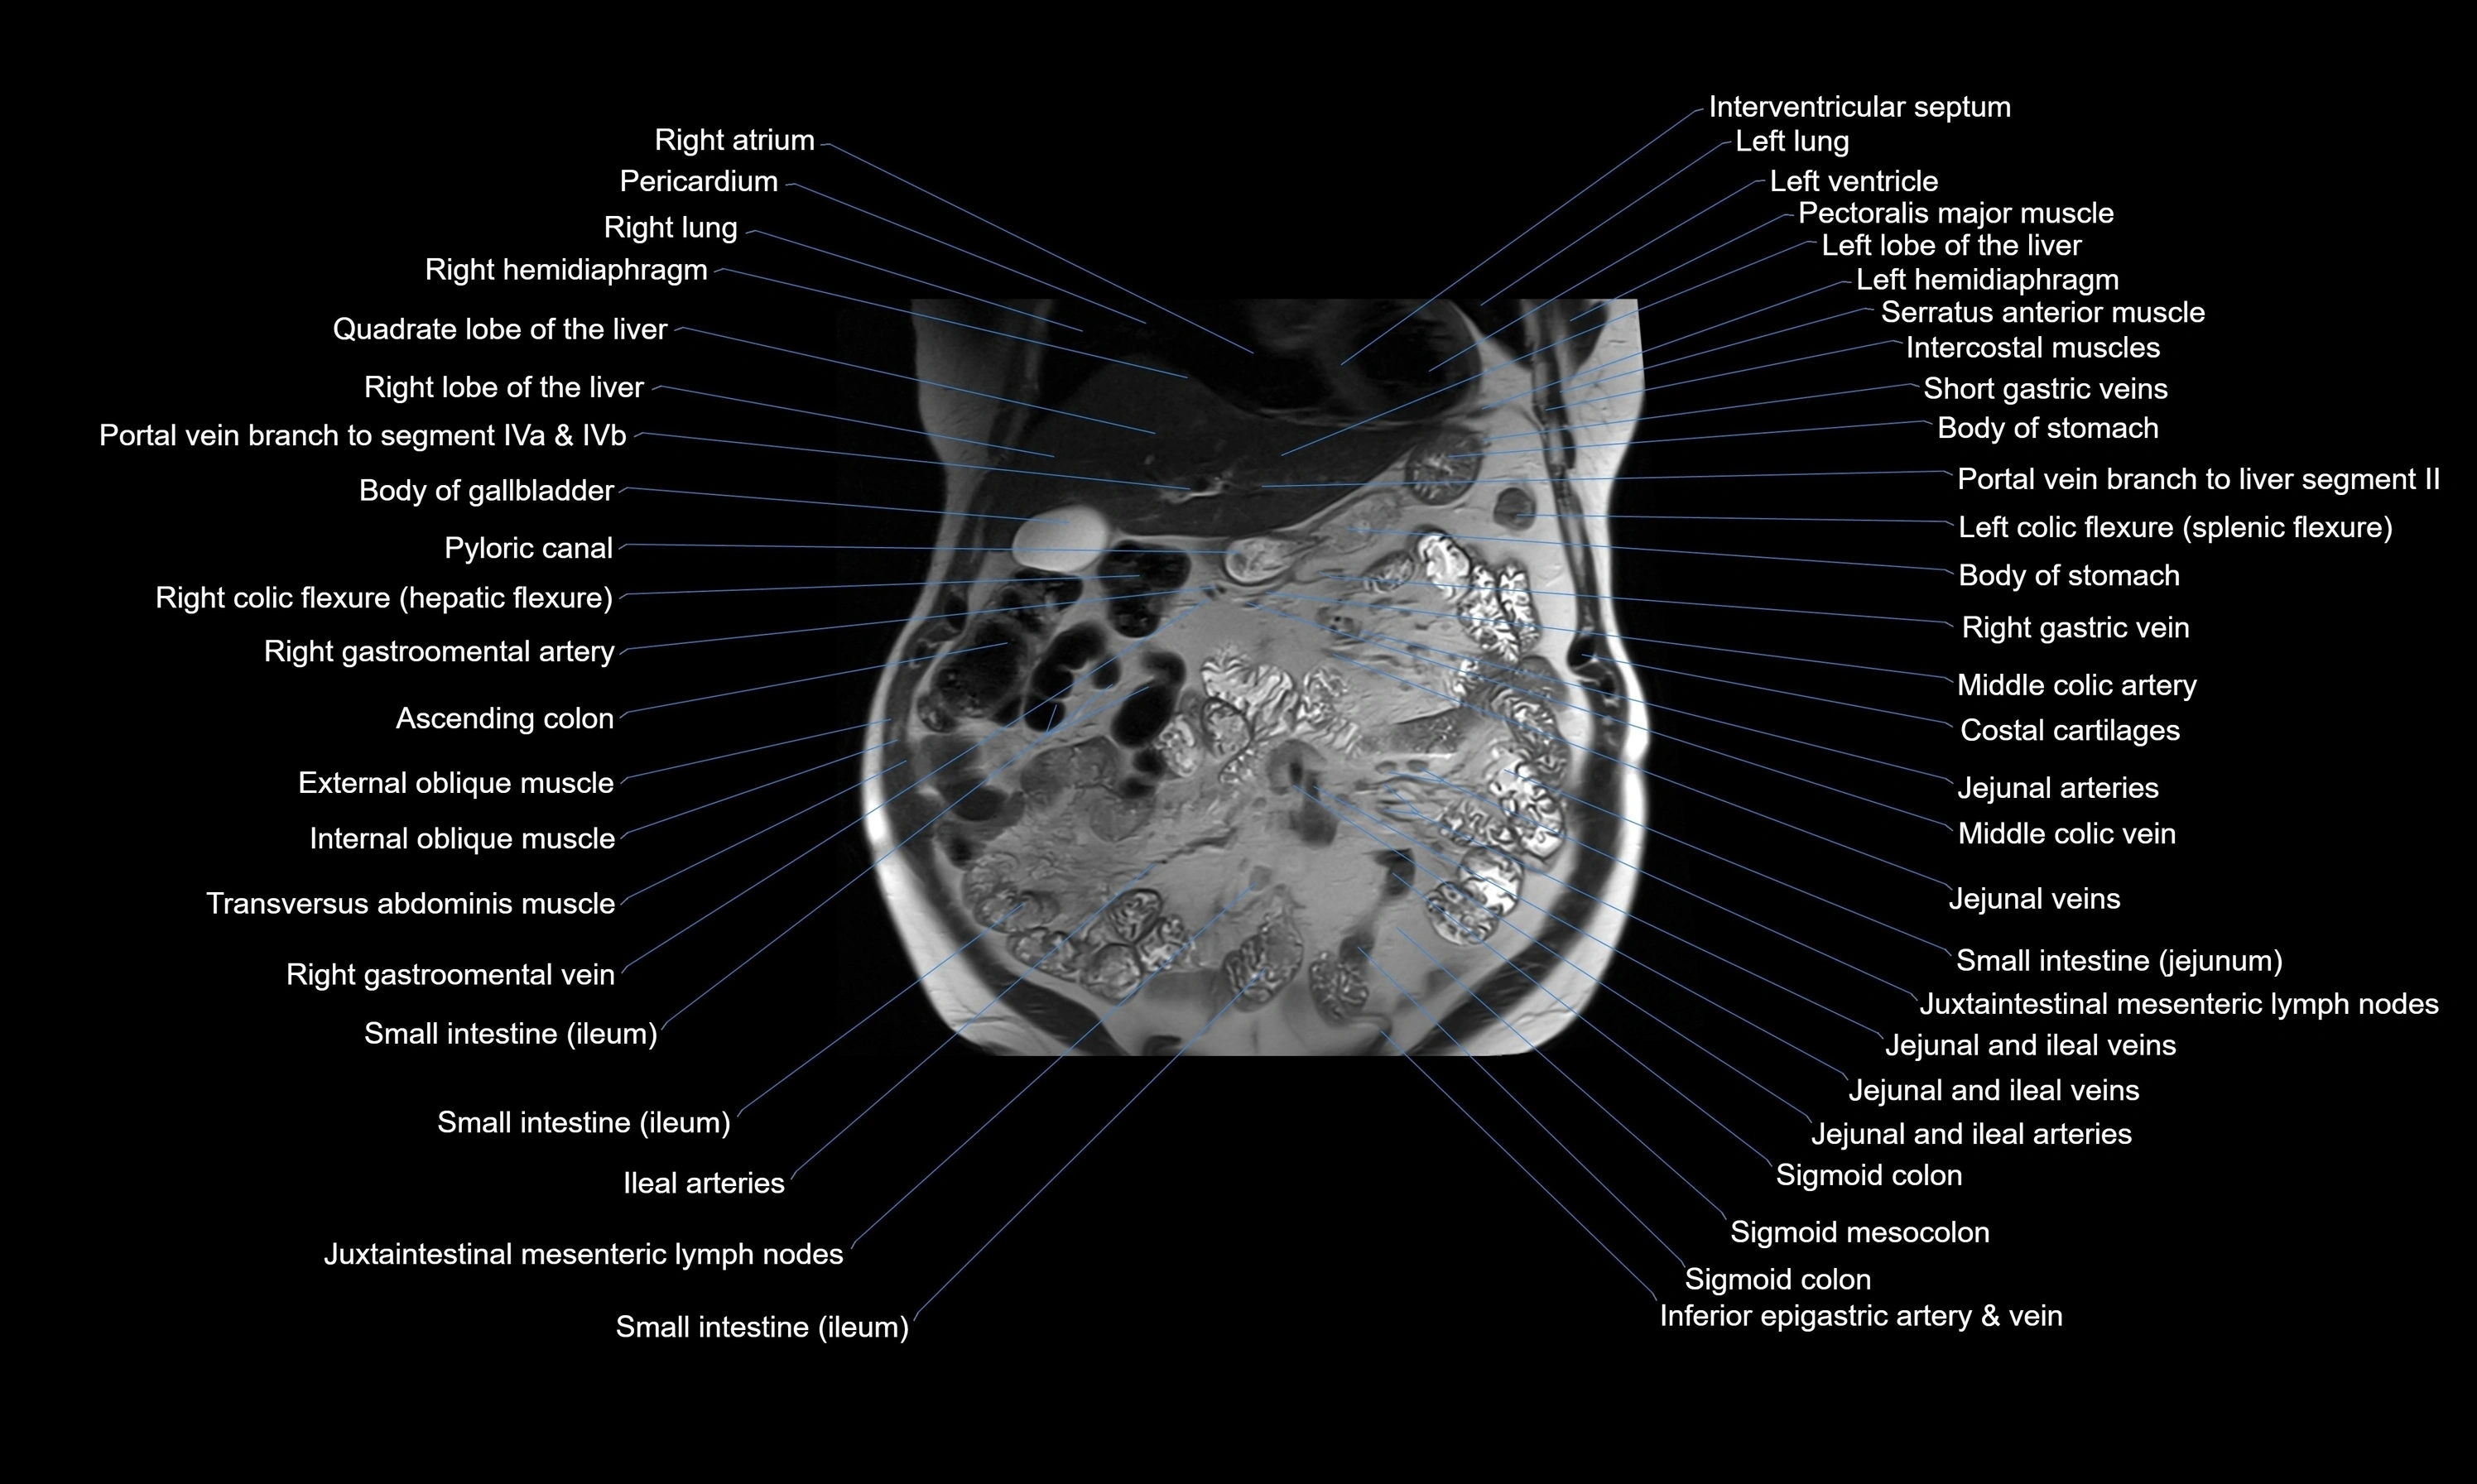

- Ascending colon

- Body of gallbladder

- Cecum

- Descending colon

- External oblique muscle

- Ileal arteries

- Internal oblique muscle

- Jejunal arteries

- Left colic flexure (splenic flexure)

- Middle colic artery

- Right colic flexure (hepatic flexure)

- Small intestine

- Transversus abdominis muscle